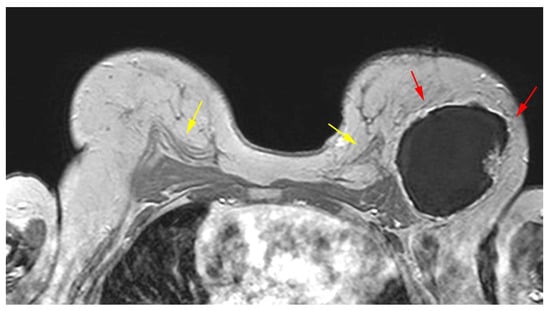

5.2.4. Capsular Contracture

- Grade I—normal soft tissues implant texture;

- Grade II—firm texture with normal contour;

- Grade III—firm texture with altered contour;

- Grade IV—firm texture with altered contour with concomitant pain [75].

| Thickened capsule | Irregular | Capsular contracture | |